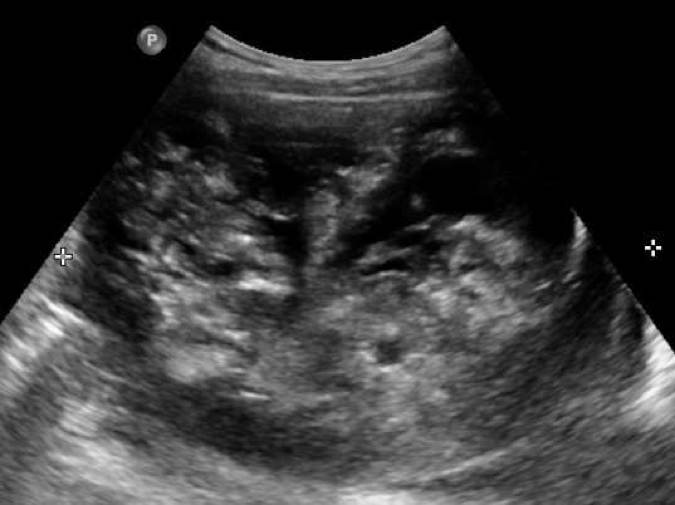

Gulesäckstumör är en ovanlig och högmalign tumör, som ofta uppträder hos unga kvinnor (vanligen 10–30 år). Stora studier saknas som beskriver ultraljudsmorfologin eftersom tumören är ovanlig, men enligt fallbeskrivningar är tumören oftast unilateral, stor (10–20 cm), solid och välvaskulariserad. Nekros kan förkomma. Se bild 4.

Bild 4. Gulesäckstumör, ”Yolksac tumor/endodermal sinus tumor”, hos 25-årig patient som sökt vård pga. blödningsrubbningar, förhöjt AFP.